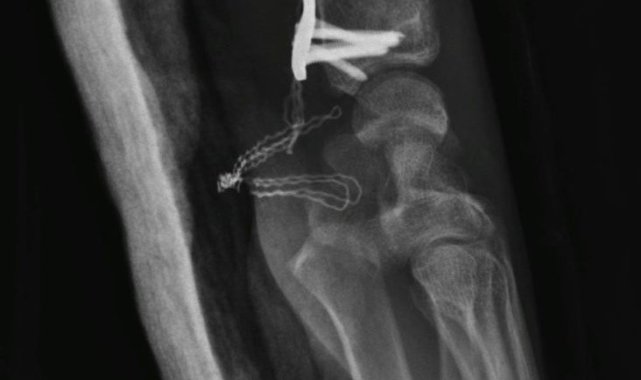

Eskişehir'de ara sokaktan çıkan otomobile çarparak ağır yaralanan 20 yaşındaki motosiklet sürücüsünün babası, oğlunun sağlık durumunun iyiye gittiğini söylerken, motosiklet kullanıcılarına da ekipman tavsiyesinde bulundu.25 Eylül günü Gündoğdu Mahallesi Cumhuriyet Bulvarı'nda yaşanan kazada, Şenel Sokak'tan bulvara çıkan Birol T. idaresindeki 34 HBF 007 otomobile, 20 yaşındaki Yusuf Gündoğmuş idaresindeki 26 AIZ 906 plakalı motosiklet yandan çarpmıştı. Kazada iki sürücü de yaralanırken, 20 yaşındaki motosiklet sürücüsünün sağlık durumu ağır olduğu öğrenilmişti. Kazadan sonra Eskişehir Şehir Hastanesi'nde uzun bir süre yoğun bakımda yatan ve birden fazla ameliyat geçiren Gündoğmuş, adeta ölümden döndü. Yoğun bakım tedavisi sırasında genç motosiklet sürücüsünün ailesinin sürekli dua ettiği öğrenildi.Oğlu ölümden dönen baba doktorlara teşekkür ettiGeçirdiği operasyonlar sayesinde kritik dönemi yavaş yavaş atlatan ve bilinci açılan Yusuf Gündoğmuş'un tedavisine sevk edildiği Eskişehir Osmangazi Üniversitesi Tıp Fakültesi Hastanesi'nde devam ediliyor. Genç motosiklet sürücüsünün 45 yaşındaki babası Hidayet Gündoğmuş, oğlunun iyileşmesi sebebiyle önce Allah'a sonra emeği geçen doktorlara minnettar olduğunu dile getirdi. Hem Eskişehir Şehir Hastanesi'nde hem de Eskişehir Osmangazi Üniversitesi Tıp Fakültesi Hastanesi'nde doktorların oğluna iyi baktığını söyleyen baba Gündoğmuş, oldukça mutlu olduğunu dile getirdi. Oğlu gibi kendisinin de motosiklete tutkun olduğunu söyleyen Hidayet Gündoğmuş, kaza görüntülerini izlediğinde ekipmanın ne kadar önemli olduğunu bir kez daha anladığına dikkat çekti. Biri kız olmak üzere üç çocuk babası Gündoğmuş, kendi gibi motosiklet tutkunu olan çocuklarına ekipman kullanmayı ısrarla söylediğini ve Yusuf Gündoğmuş'un da ekipmanları sayesinde hayatta kaldığını ifade etti"Rabbim kimseye yaşatmasın"Konuyla alakalı konuşan Hidayet Gündoğmuş, "Şükürler olsun, her gün daha iyiye gidiyoruz, daha iyiyiz. Şehir hastanesiyle ameliyatlarımız bitti. Oradaki doktorlarımıza çok teşekkür ederim, çok ilgilendiler. Tıp fakültesindeki plastik cerrahide estetik ameliyatlarımız var. Allah'a şükür her gün daha iyiye gidiyoruz. Çocuğumuz ayağa kalktı, sağlığı yerinde. Kaza anını gördüğümde anlatamam; kendim Diyarbakır'daydım, uzun yoldaydım. Rabbim kimseye yaşatmasın. Kötü bir duygu; çok şey demek isterim. Ben kendim de motor kullanıyorum. Bizde aile boyu hepimizde motor var. Kendim 18 yaşından beri kullanırım. Şükürler olsun bugüne kadar bir kazam olmadı. Çocuklarıma istedikleri motoru aldım. Amcalarında da var, amcasının çocuklarında da var. Bizim Eskişehir'imizin halkı motora karşı biraz daha duyarsız. Motor kullanan arkadaşlarımız, kardeşlerimiz de cahil. Arabaların sağından soldan trafikte çok geçerim, "geçivereyim" gibisinden hareketler var. Biz halk olarak yaya iken trafikteki taşıtlara kızarız, arabadayken yayalara kızarız. Halk olarak çok bencil bir toplumuz. Eğitim desem eğitim değil, kültür desem kültür değil. Herkes kendi çıkarları veya bencil davranışları yüzünden trafikte birçok kaza görüyoruz. Her gün kazalar oluyor. Motora binen özellikle gençlerimizi ve kuryelerimizi acele etmemeleri konusunda uyarıyorum" diye konuştu."Bedeli biraz ağır oldu ama şükürler olsun Rabbime"Trafikte sıklıkla seyreden kuryeler başta olmak üzere motosiklet kullanıcılarını uyaran Gündoğmuş, şöyle devam etti;"Özellikle kuryeler, insanların siparişlerini iki dakika önce götüreceğim diye kendi hayatlarını, kendi canlarını riske atmasınlar; sevdiklerini üzmesinler. Biz böyle ağır bir kaza yaşadık; keşke yaşamasaydık. Bedeli biraz ağır oldu ama şükürler olsun Rabbime. Daha iyiyiz. Her gün daha iyiye gidiyoruz. Herkes dikkatli olsun. Yani motora binenler de araçlara karşı dikkat etsinler. Araç kullanan vatandaşlarımızın da motorları görmelerini istiyorum.""Evladımız gayet iyi, sağlıklı, yerinde"Oğlunun tedavi sürecini anlatan Hidayet Gündoğmuş, şunları kaydetti:"Beş gün entübe edildi. Ne olacağı belli değildi çıkmama ihtimali vardı. Şükürler olsun doktorlarımız ve Rabbim sayesinde entübeden çıktık. Hatta ciğerin birisinde infilak vardı; ciğer sorunumuzdan dolayı özellikle yoğun bakımda entübediydik. Beş günün sonunda ciğerleri toparlamaya başladı; entübeden çıkarttılar. Solunumu normale döndü. Sırayla sağlığı yerine gelmeye başladı. Bir hafta sonra kolundan ameliyat oldu platin koydular. Omurilikten ameliyat olduk. Omuriliğinde ilk röntgende tek kırık gördüler; üç kemiği birbirine bağlayacaklardı. Sonradan ikinci röntgende üç kırık olduğunu gördük; yedi kemiği birbirine bağladılar. Omuriliğe platin takıldı. 14 tane civatamız var. Şükürler olsun doktorlarımıza, Allah razı olsun. Evladımız gayet iyi, sağlıklı, yerinde. Artık işte suratta, çenede, burunda, elmacık kemiklerinde parçalı kırıklarımız var. Osman Gazi Fakültesi'nde Allah'ın izniyle buradaki hocalarımıza, önce Rabbim'e sonra hocalarımıza emanet çocuğumuz. İnşallah daha iyi olacağız; ben kendi adıma söylüyorum. Çocuğuma, her motora bindiklerinde sürekli kask ve montlarını giymelerini tembihliyordum. Giymediklerinde fırça atıyordum. Eskişehir'de birçok yerde tanınırız, tanırlar. Sevenimiz, eşimiz, dostumuz çok; uyarırlar, telefon gelir, haber verirler. Her duyduğumda, gördüğümde söylerim. Sağ olsun, çocuğum da o gün beni dinlemiş, kaskını takmış. Şükürler olsun ki takmış; takmasaydı o gün, o kazada belki çocuğumuzu kaybederdik."